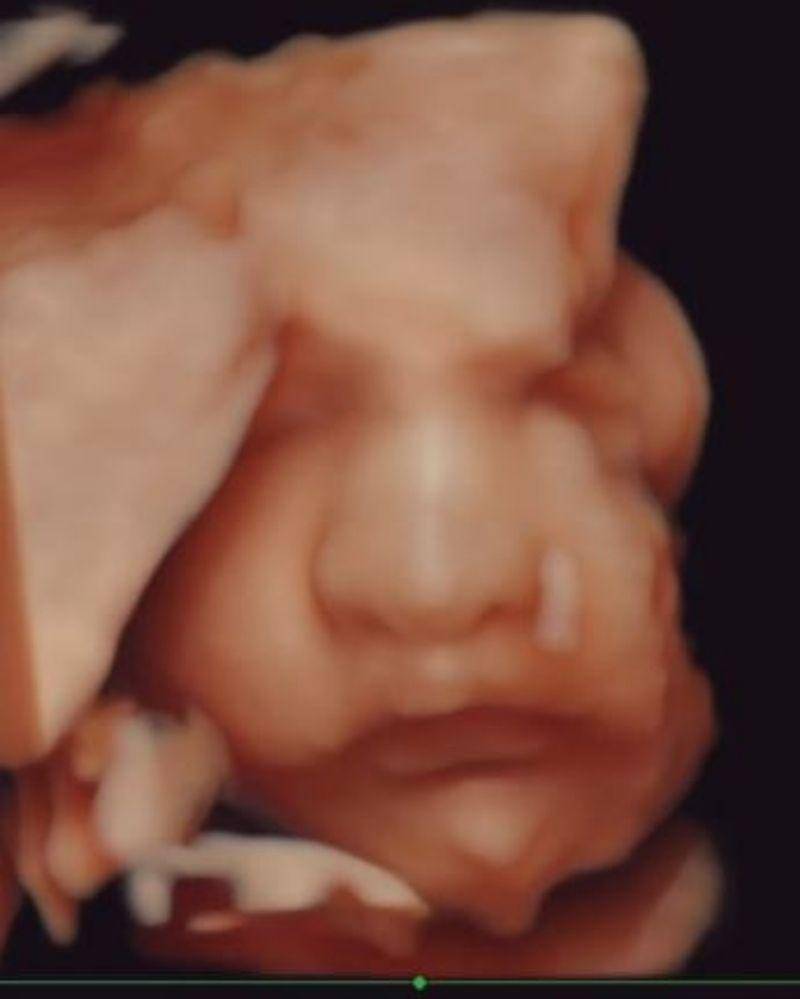

15. Ardashir Behrouz Al Barraq, putra Angbeen Rishi dan Adly Fayruz

Pasangan Adly Fairuz dan Angbeen Rishi melahirkan anak pertama mereka yang berjenis kelamin laki-laki pada 1 Januari 2021. Pasangan ini memberikan nama indah, yaitu Ardashir Behrouz Al Barraq.

Saat mengandung Ardashir, Angbeen Rishi juga sempat membagikan cuplikan video hasil USG baby Ardashir. Dari unggahan tersebut, banyak warganet yang terpesona dengan hidung mancung Ardashir.